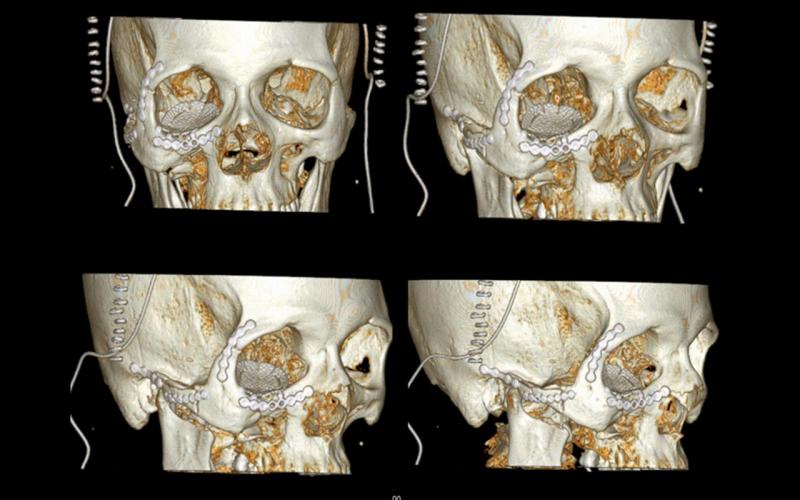

Diagnosis and treatment of dysgnathia, and orthognathic reconstructive surgery, genioplasty, maxillo-mandibular advancement/set-back, and surgical correction of facial asymmetry (See Images Below)